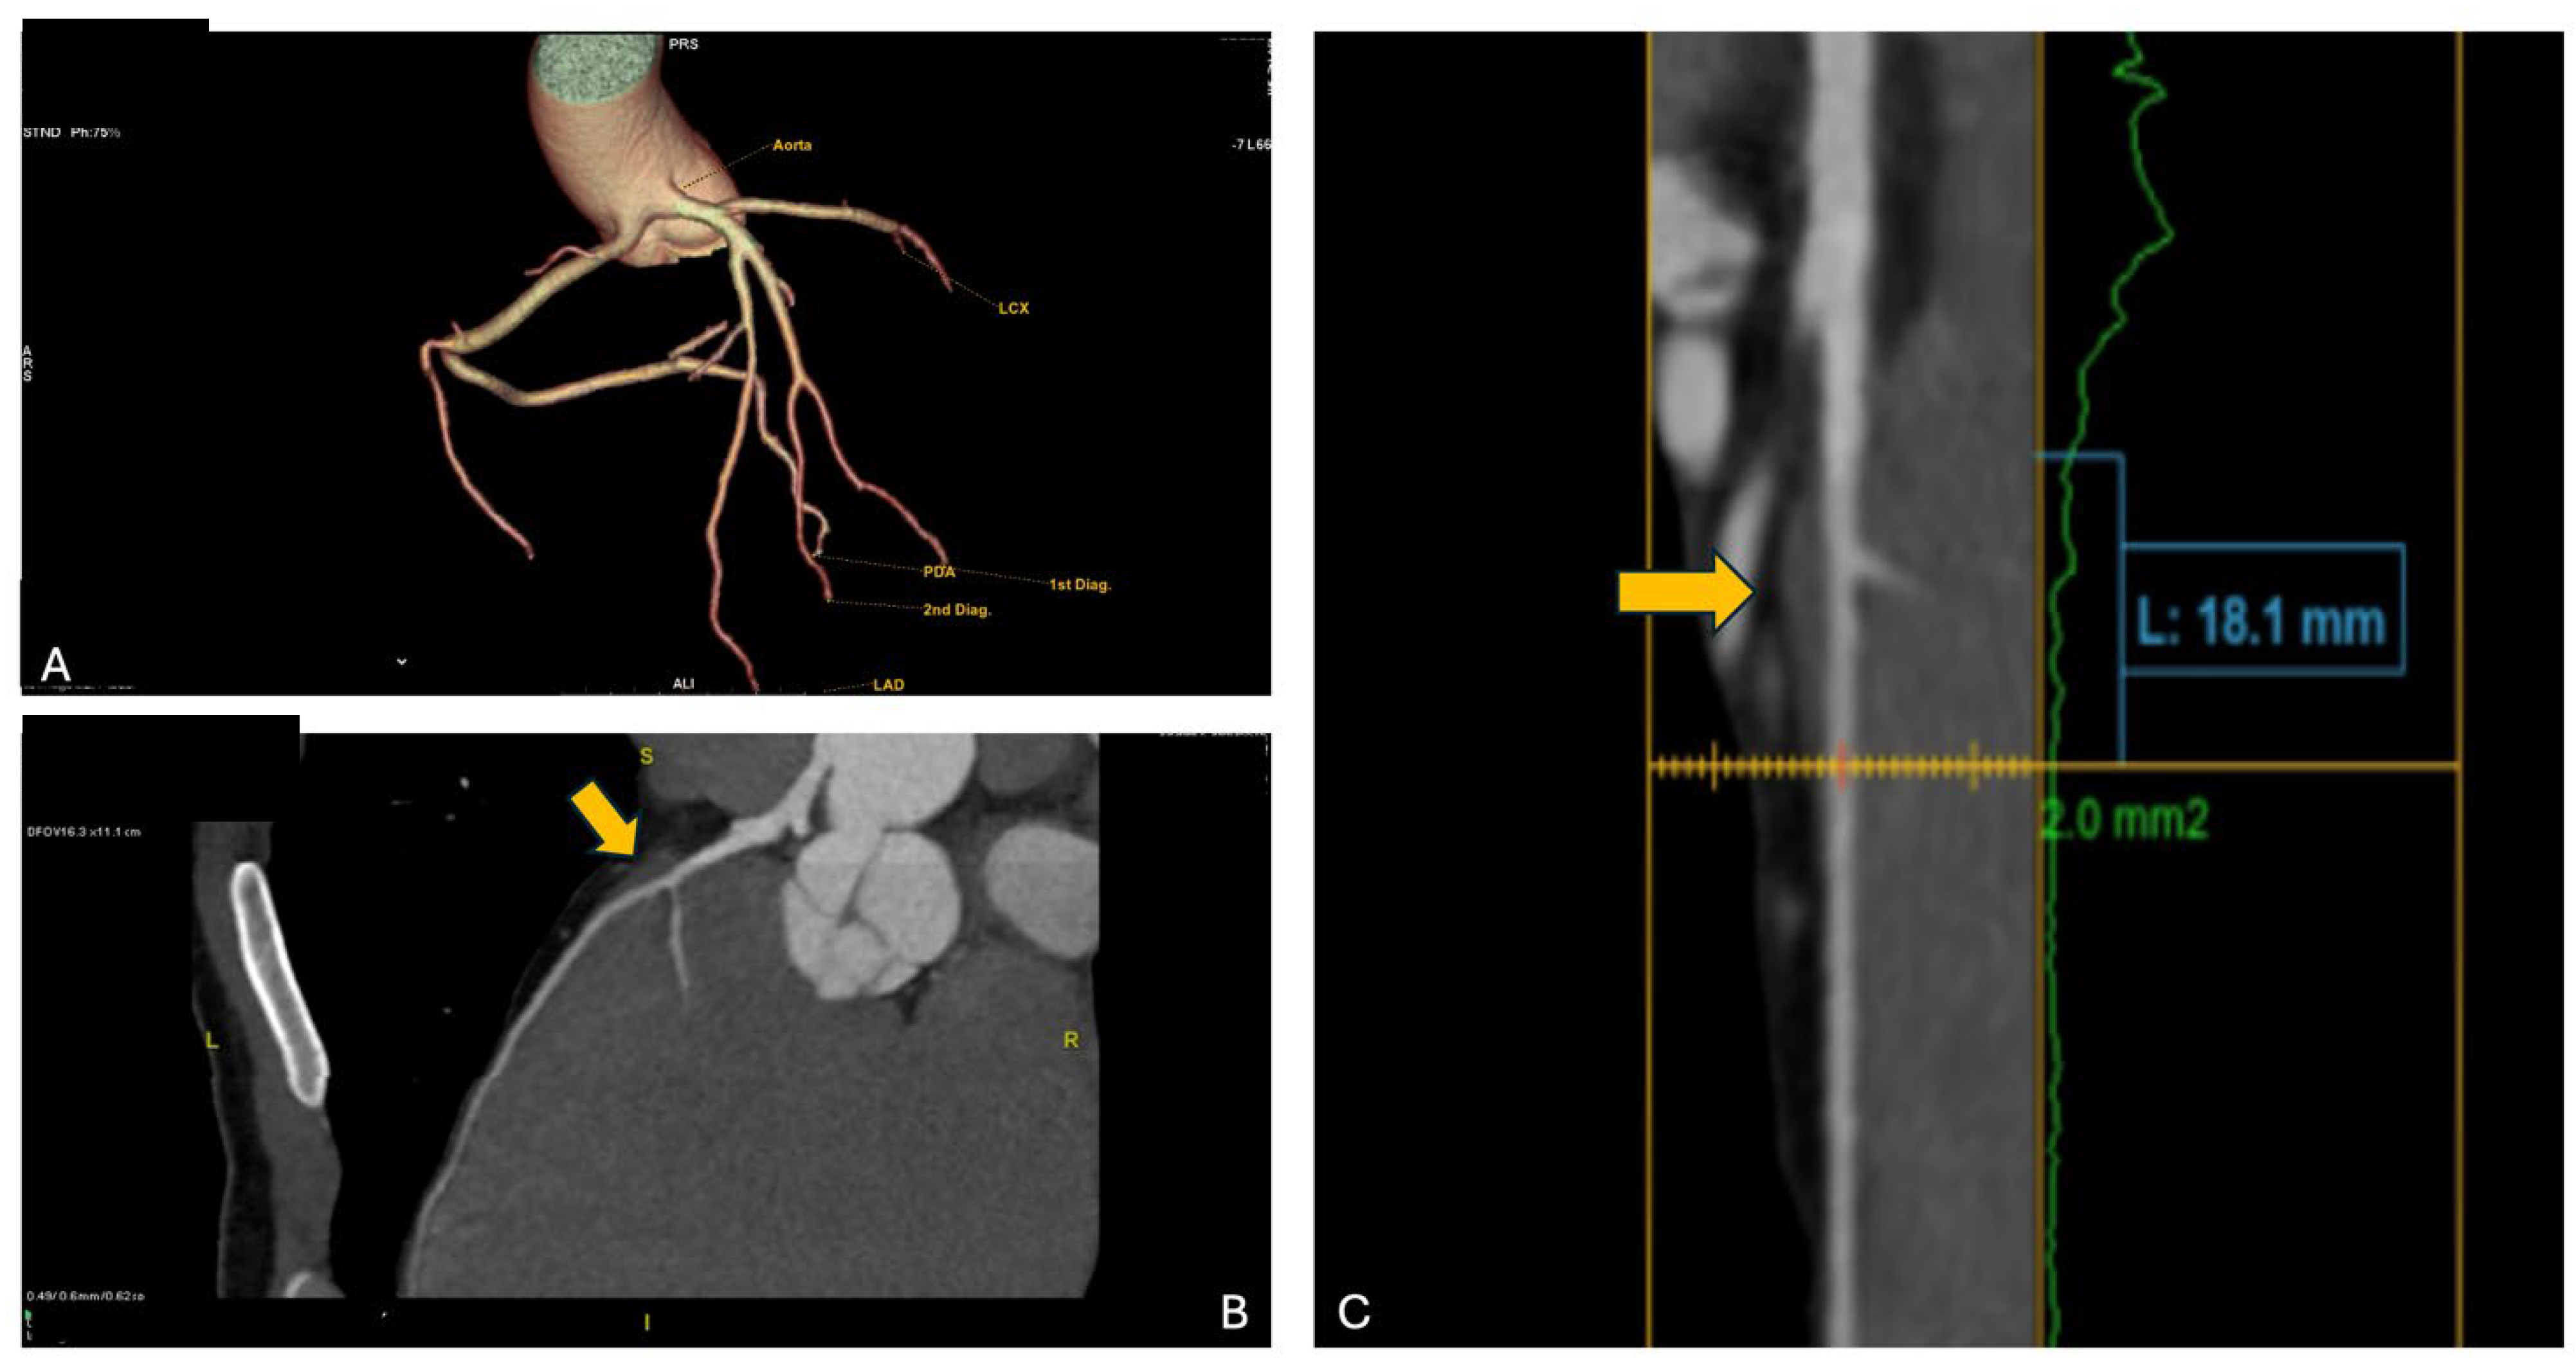

Consequently, the athlete underwent CCTA which confirmed the presence of an anomalous origin of the right coronary artery and the common trunk just above the junction between the right and left coronary sinuses, with an inter-arterial course of both vessels, but no signs of intramural course (absence of “slit-like” ostium or reduction in diameter at the origin and proximal segment). It is shown in Figure 5. Furthermore, the presence of a very short first segment of the LAD was noted, 2 mm deep and 18 mm long, with the first diagonal branch originating very proximally and a myocardial bridge over the second segment.

Figure 5. The CCTA of the patient from case 5. In panel A, the common origin of the right and left coronary arteries from the left Valsalva sinus is shown; in panels B and C, the yellow arrows indicate the presence of the intramyocardial bridge on the LAD.